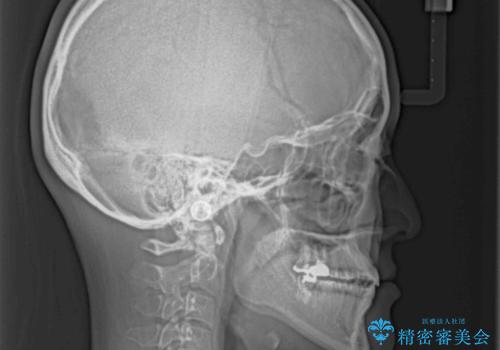

オープンバイトと前歯のデコボコをインビザライン矯正で解消

- 前歯の開咬を気にして来院された患者様です。

開咬の治療は、前歯を閉じるように動かすとともに、上下臼歯を圧下(骨内にめり込ませる)させることで進めて行きます。

インビザラインは臼歯の圧下を効果的に行えるため、インビザラインを用いて矯正治療を行うこととしました。

オープンバイトは舌の突出癖により誘発され、治療後も突出癖が残っている容易に後戻りしてしまいます。

治療期間を短縮するためにも、舌突出癖の改善が極めて重要となります。